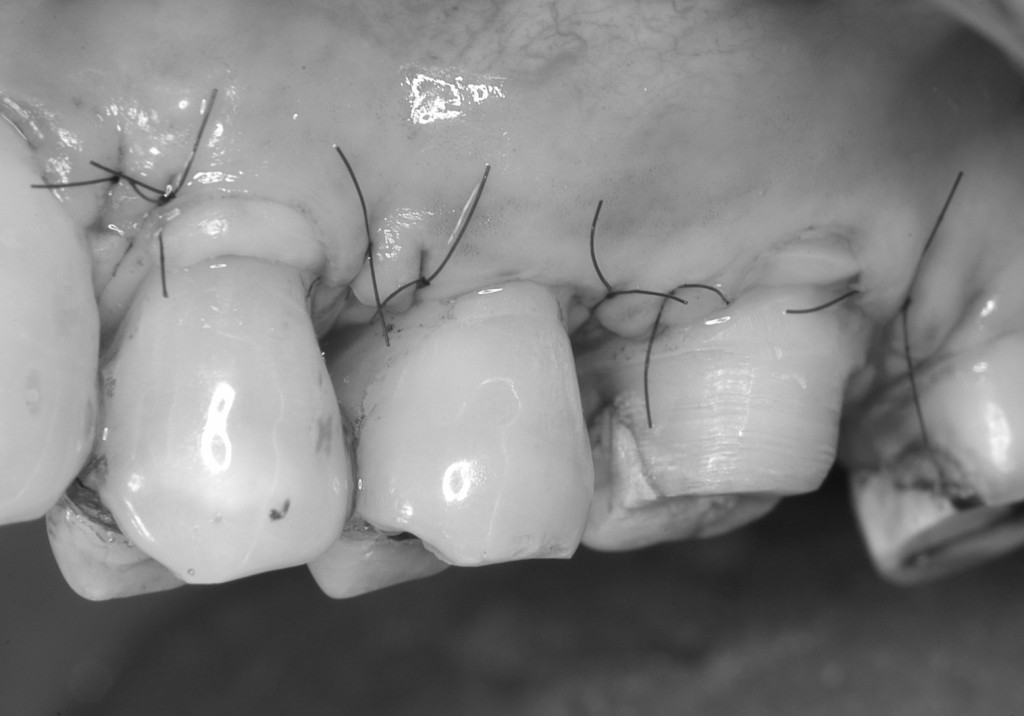

結合組織を縫合しました。

治癒後の写真は,このページ一番上の治療後の写真をご覧ください。

術前に比較して,露出していた根っこの面積が少なくなっているのがわかります。ご本人も大変喜ばれていました。